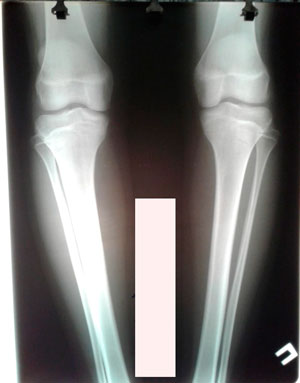

Исходник - 15 лет. Павлодар.

Дата операции - 15.06.2019г.